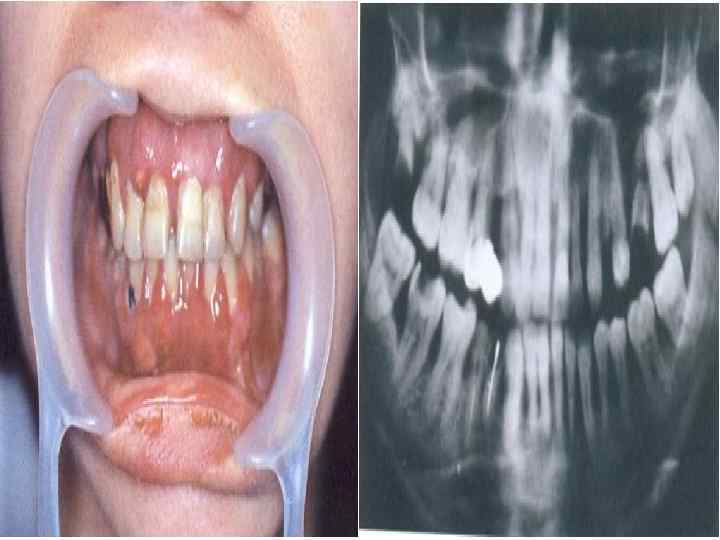

Клиникалық белгілері • Жылдам дамитын пародонт қабынуының атипиялығы пародонт тіндерінің бұзылысқа ұшырауы жастық шақта басталады: 17– 20 жастан, дәстүрлі емге берілмейді және нәтижесі нашар. .

• ЖДПҚ клиникалық белгілері : • Пародонт тіндеріндегі деструктивті өзгерістер балалық шақтан кейінгі немесе ерте жастық шақта басталады. • Пародонттағы қабыну үрдісінің төмендігіне қарамастан, сүйек тінінің жайылған деструкциясының болуы • Басқа науқастармен салыстырғандағы бірдей тіс қақтарында, пародонттың ауыр бұзылыстары • Емнің нәтижесіздігі немесе нәтиженің қысқа мерзімділігі.

• Пародонт қабынуының бірінші симптомы(тіс тазалау кезінде қызылиек қанауы) сүйек тіні деструкциясының пайда болуына дейін 5– 6 жыл бұрын пайда болады. Көбіне науқастар емханаға аурудың ауыр кезеңдерінде, тіс қозғалғыштығын алғашқы симптом ретінде шағымданып келеді. Ауру ағымы толқынтәрізді , қысқа ремиссия және жиі өршумен сиппатталады(1 рет 3 айда).